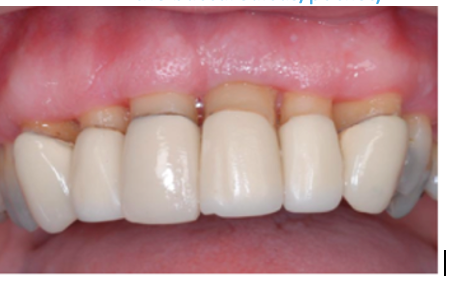

22

Q

what type is this

A

recession type 1

23

what type is this?

recession type 3

24

recession type 2